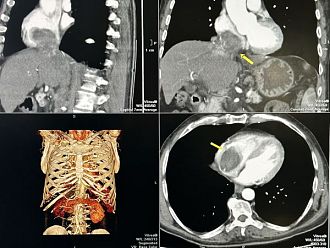

След постъпването на пациента в лечебното заведение е направен скенер, от който се установяват злокачествените образувания в кухините на сърцето и наличието на две огромни туморни огнища в черния дроб.

Туморът с размери 7 на 9 см. е ангажирал и изпълнил почти изцяло кухината на дясното предсърдие на сърцето и е застрашавал да запуши белодробните артерии и белия дроб.

Туморът се разпространява и в коремната област, като обхваща и запушва прехода на долна празна вена, преминаваща през черния дроб. Размерът на туморното образувание в този участък е с дължина 17 см и широчина 3 см.